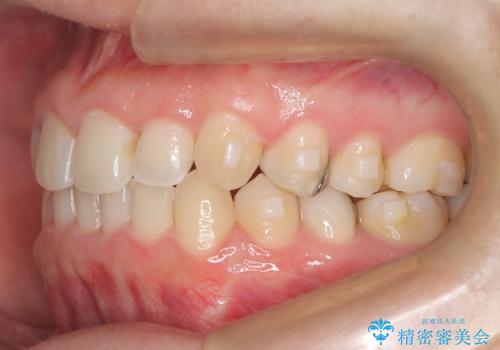

- 下の歯のがたつき(叢生)、真ん中(正中)が右にずれていることを主訴に来院されました。右上前から3番目の永久歯が埋まっている(埋伏)していることから正中は可能な限り合わせることをゴールとしてマウスピースでの矯正治療を選択しました。

今回の矯正治療では、透明なマウスピース型の装置インビザラインを使用しました。がたつきをとるため、安全性が確保できる範囲で歯と歯の間を少し削り必要なスペースを確保しました。